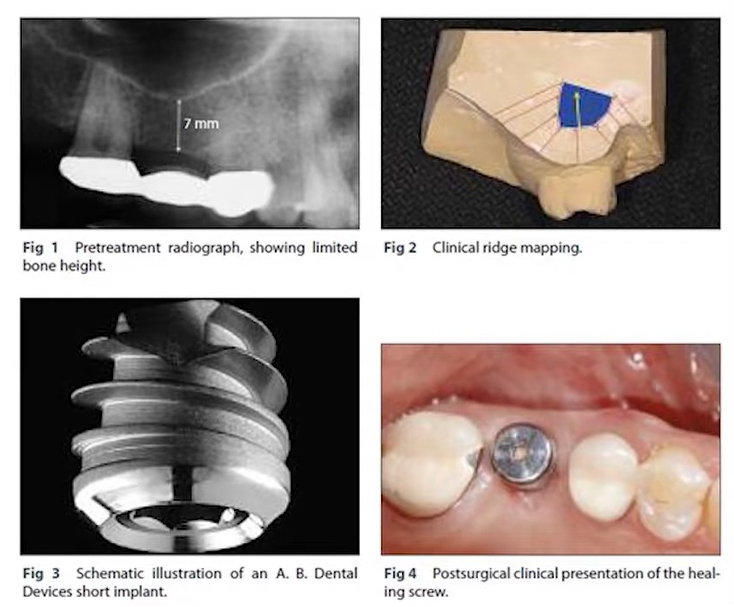

Let’s start with a clinical case described by Israeli colleagues in the following article:

“Short dental implants in reduced alveolar bone height”

A large 6 mm diameter, 6 mm long implant with a standard thread profile was used. A standard profile means threads are sharper at the apex and become smoother toward the neck.

The available bone height was 7 mm to the floor of the maxillary sinus (see the illustration below).

Description of the situation: bone conditions, implant design, condition with a healing cap. YouTube/ Implantarium/ Rauf Aliyev

The implant was placed subcrestally, 1 mm below the marginal bone level. The implant apex was positioned almost at the maxillary sinus floor, as seen in the upper left slide.

Everything seemed fine: The implant was stable. However, a 12-month follow-up showed slight bone resorption, and the implant neck was exposed by about 1 mm.